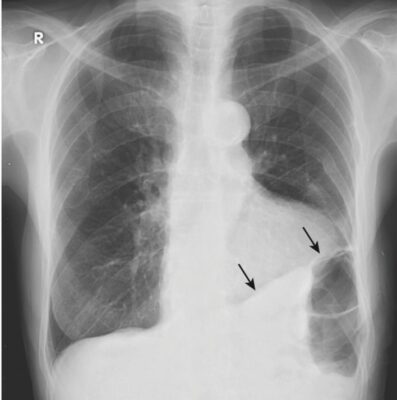

Mờ các góc sườn hoành (Blunting of the Costophrenic Angles)

Khi tràn dịch dưới phổi phát triển về kích thước, trước tiên nó sẽ lấp đầy và do đó làm mờ rãnh sườn hoành sau, có thể nhìn thấy ở phim phổi nghiêng. Điều này xảy ra với khoảng 75 mL chất dịch (Hình 4).

- Khi tràn dịch đạt đến kích thước khoảng 300 mL, nó làm mờ góc sườn hoành bên, có thể nhìn thấy trên phim X quang ngực thẳng (Hình 5).

- Cạm bẫy: Dày màng phổi do xơ hóa cũng có thể gây mờ góc sườn hoành.

- Giải pháp: Sẹo (ví dụ, do nhiễm trùng, phẫu thuật hoặc máu trong khoang màng phổi trước đó) đôi khi tạo ra hình dạng mờ kiểu dốc trượt tuyết đặc trưng, không giống như hình dạng như sụn chêm (meniscoid) của tràn dịch màng phổi (Hình 6).

- Dày màng phổi sẽ không thay đổi vị trí khi bệnh nhân thay đổi tư thế, khác với hầu hết các trường hợp tràn dịch.